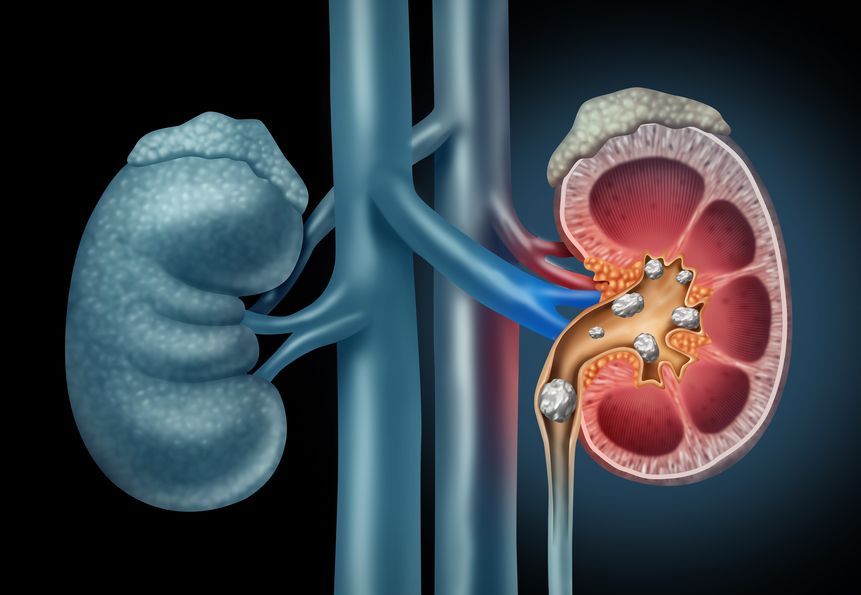

Die Organe altern mit dem Menschen und deren Funktionen sind zunehmend beeinträchtigt. Am häufigsten ist dieses Phänomen bei den Nieren zu sehen, die bereits nach dem 40. Lebensjahr altern – jedes Jahrzehnt verlieren sie 10 % ihrer derzeitigen Verarbeitungskapazität. Kein Wunder also, dass so viele Senioren an chronischem Nierenversagen leiden.

In Polen klagen etwa 4,5 Millionen Menschen über Nierenprobleme. Dies betrifft vor allem ältere Menschen. Warum ist diese Situation so alarmierend? Immerhin sind Nieren doch ein so kleines Organ, dessen Einfluss auf den Körper nur sehr gering ist. Falsch! Nieren sind trotz ihrer Größe eines der wichtigsten Organe unseres Körpers. Jeden Tag filtern und reinigen gut funktionierende Nieren bis zu 1500 Liter Blut. Die Aufgabe dieses 120 Gramm schweren Organs ist auch ein Schutz für den Menschen vor Austrocknung, es entfernt überschüssige Toxine aus dem Körper und vermeidet eine übermäßige Konzentration von Elektrolyten.